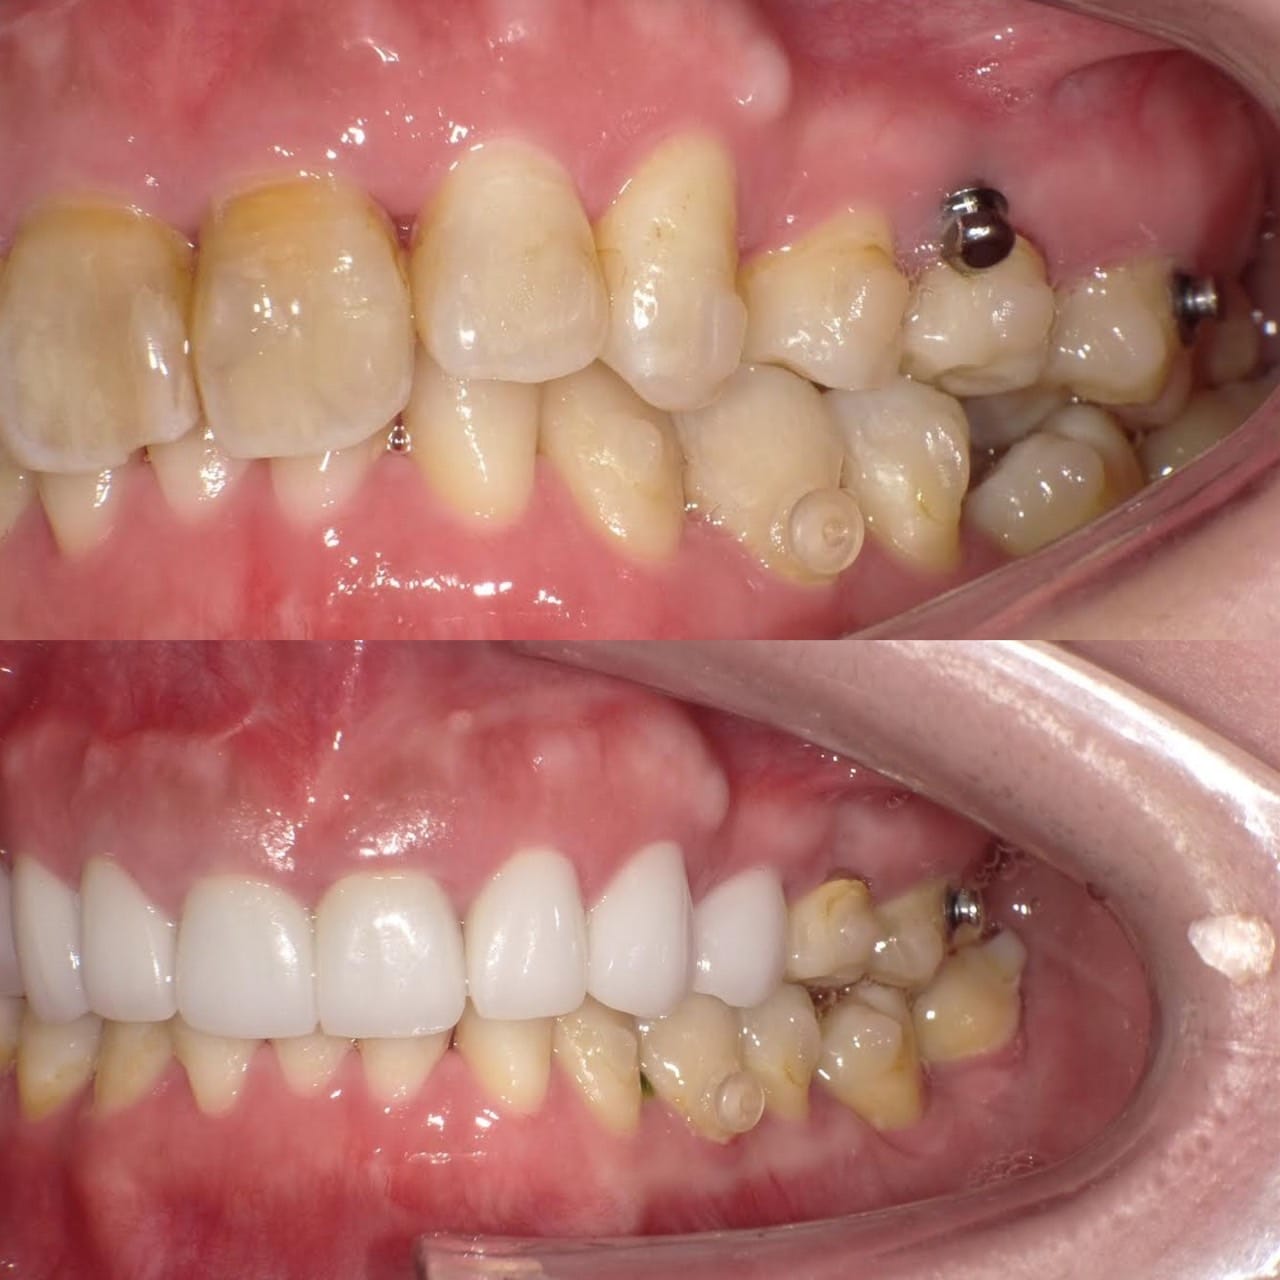

Case011 – インプラント

前医でインプラントの埋入角度が悪く、インプラント周囲炎になってしまった患者様の症例です。

インプラントが虫歯になることはありませんが、インプラント周囲炎というインプラントの歯周病にはなります。

インプラント周囲炎の主な原因は汚れ(菌)と力です。このように斜めに埋入されているインプラントは、真っ直ぐ埋入されているものに比べて汚れも溜まりやすく、噛む力も斜めにかかってしまうため、インプラント周囲炎になるリスクが大幅に高くなります。

この患者様は内側の骨が大幅に溶けてしまっていたので、前のインプラントを撤去して、骨を再生させると同時にインプラントを正しい位置と角度で埋入し直しました。溶けてしまっていた骨が治っていることもレントゲンでご確認いただけるかと思います。

インプラントは「どこの位置にどのような角度で入れるか」によって、一生使い続けられるかどうかの期待値が大きく異なります。値段だけを基準にクリニックを決めるのではなく、信用できる歯医医師と治療を進めることをお勧めします。

担当 理事長 佐藤悠野